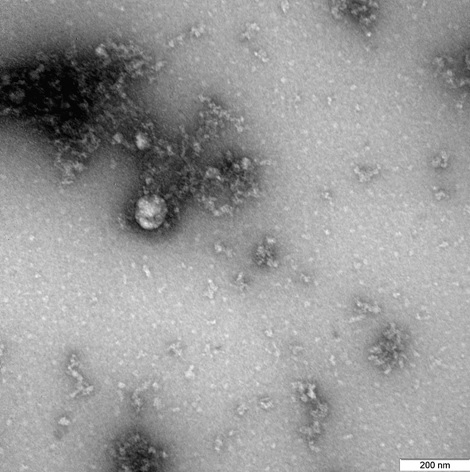

Ученые Роспотребнадзора сфотографировали «британский» штамм коронавируса

Первое в мире изображение «британского» штамма коронавируса сделано учеными ФБУН ГНЦ "Вектор" Роспотребнадзора в ходе изучений образца, выделенного у пациента в декабре 2020 года. Ученые изучают свойства нового штамма, его структурные особенности и проявления в экспериментальных моделях на животных.